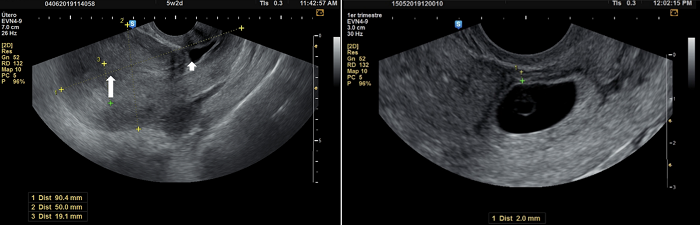

Variables medidas. Edad, número de partos y cesáreas previas, edad gestacional, índice de masa corporal (IMC), nivel β-hCG (mIU/ml), hemoglobina al ingreso y al alta (g/dL), tamaño de la masa gestacional (mm); grosor del miometrio residual (mm), definido como el grosor de la capa de miometrio que se encuentra entre el saco gestacional y la serosa vesical (Figura 1); presencia de latidos cardiacos embrionarios al tiempo del diagnóstico; tipo de tratamiento recibido (médico o quirúrgico); complicaciones intra o posoperatorias; tiempo de desaparición de la (β-hCG, y desenlace reproductivo a largo plazo (gestación y parto después del tratamiento).

En cuanto a las características demográficas, clínicas y de laboratorio, la mediana de la edad fue de 35 años, con un rango intercuartílico (RIQ) de 30,5-40. El número de partos y de cesáreas previas tuvo una mediana de 2 (RIQ = 1-2). La mediana de la edad gestacional al momento del diagnóstico fue de 7 semanas (RIQ = 6-0,2). El nivel de la β-hCG al ingreso tuvo una mediana de 8.904 mUI/ml (RIQ = 5.903-28.165), mientras que la mediana del tiempo de normalización de la β-hCG fue de 16 días (RIQ = 7-30). La hemoglobina al ingreso tuvo una mediana de 12 g/dL (RIQ = 11-13), y al alta fue de 11 g/dL (RIQ = 10-12). El tamaño de la masa gestacional tuvo una mediana de 27 mm (RIQ = 16-42), y el grosor del miometrio residual fue de 4 mm (RIQ = 2-5 mm). El tiempo transcurrido desde la última cesárea tuvo una mediana de 3 años (RIQ = 2-5); al ingreso, 11 pacientes (64,7 %) presentaron latidos cardiacos embrionarios, y la misma cantidad de pacientes presentó sangrado vaginal (Tabla 1).